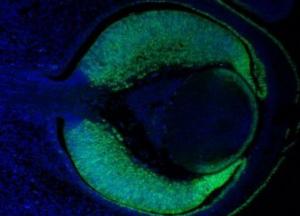

У эмбрионов человека нашли признаки старения

Чтобы проверить эту гипотезу, ученые решили измерить маркеры старости на внутриклеточном уровне. Они подсчитали, какое количество мутаций можно обнаружить в опухолях у людей разного возраста. Оказалось, что количество мутаций возрастало с самого начала жизни.

Согласно выводам ученых, организм начинает стареть с первых недель внутриутробного развития. Признаки биологического возраста накапливаются с самого начала жизни. На первых этапах развития человека отбор против унаследованных мутаций действует с максимальной силой, а затем снижается. В 9 лет уровень смертности низок, потому что отбор уже ослаб, а возрастные болезни еще не наступили.